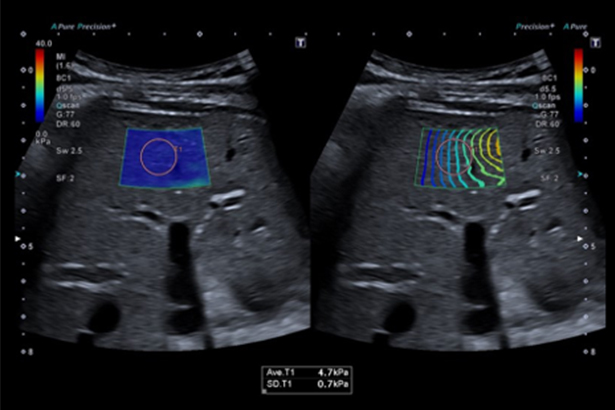

可以用于多種臨床領域,定量測量并實時顯示組織彈性值。Smart Maps 質控工具幫助顯示剪切波傳播圖并評估彈性圖質量。